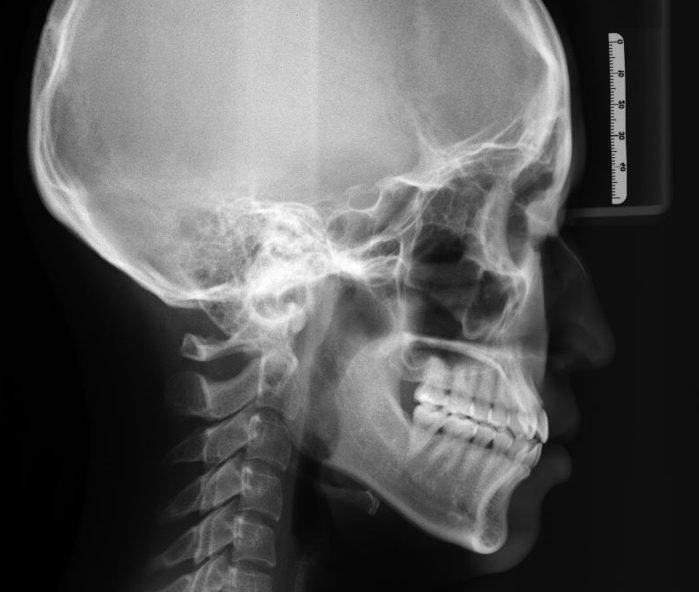

側方頭部X線規格写真(ラテラルセファロ)

お口のなかやお顔の写真撮影、口腔内3Dスキャナーによる歯型の取得、CT、各種レントゲン検査などを行います。

合わせてこちらもご覧ください≫≫≫矯正治療前に知っておくべき!セファロ分析の重要性~セファロを撮らない矯正歯科は危険?~